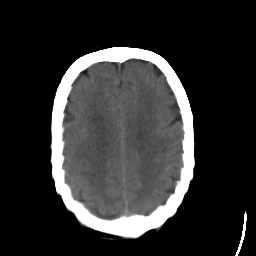

Stroke CT #1 -- Slice #18

[Home][Help][Clinical] Slice 18